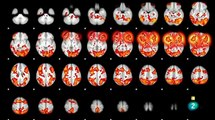

El gigante asiático está siendo víctima de una verdadera crisis en materia de salud mental, la que cobra dimensiones particularmente dramáticas por el impacto que tiene en los niños. Japón tiene la tasa de suicidio más alta entre los países desarrollados (con más de 30.000 casos al año, de los cuales 20% corresponde a menores de edad), y los expertos buscan las causas.

El psiquiatra Toshinori Kitamura explica que hace diez años se creía que no existía maltrato infantil en Japón: "Hoy se sabe que el porcentaje de niños que viven violencia física y sicológica es alto. Ellos se sienten poco cuidados y muy vigilados, lo que detona en la adolescencia variados trastornos mentales, desde depresión y ansiedad hasta otros más severos". Incluso, agrega, se ha visto el surgimiento de abuso neonatal: madres que maltratan a sus hijos recién nacidos. Junto con eso, se trata de una sociedad en donde los trastornos mentales están recién siendo abordados, por lo que no existe conciencia de que constituyen un problema que debe ser tratado. Las personas, además, no tienen la costumbre de expresar lo que sienten y las muestras de afecto son contenidas. En este escenario, dice a La Tercera el profesor Mark Radford, experto en Ciencias de la Conducta de la U. de Hokkaido, las elevadas exigencias académicas sobre los menores se hacen sentir: "Estamos viendo cada vez más casos de niños que simplemente no quieren ir al colegio debido al estrés y a los índices de violencia escolar". La falta de comunicación al interior de las familias, las largas jornadas de trabajo, el estrés de los adultos y los videojuegos también tendrían su cuota de responsabilidad: "Creo que la exposición a videojuegos ultraviolentos, unido a una falta de sentido de la vida y de conexión con la familia, ha contribuido a alienar a los niños, haciendo que pierdan conciencia de quiénes son ellos mismos y mermando su capacidad para sentir emociones", concluye Radford.